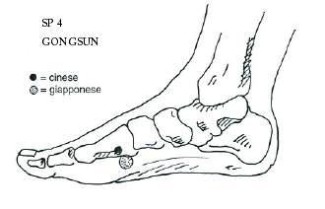

Il Punto di Apertura è PC-6 nei guan (barriera interna), il punto Associato è SP-4 gong sun (nonno e nipote) collegato al meridiano Chong Mai.

SP-4 gongsun

Rafforza le funzioni di Milza e Stomaco, quindi interviene sulle sorgenti del Qi e del Sangue post-natale. Esso interviene per creare il Sangue, rafforzare il Qi e lo Yang, trasformare l'Umidità. Va frizionato con energia ed è molto doloroso in gran parte dei casi.